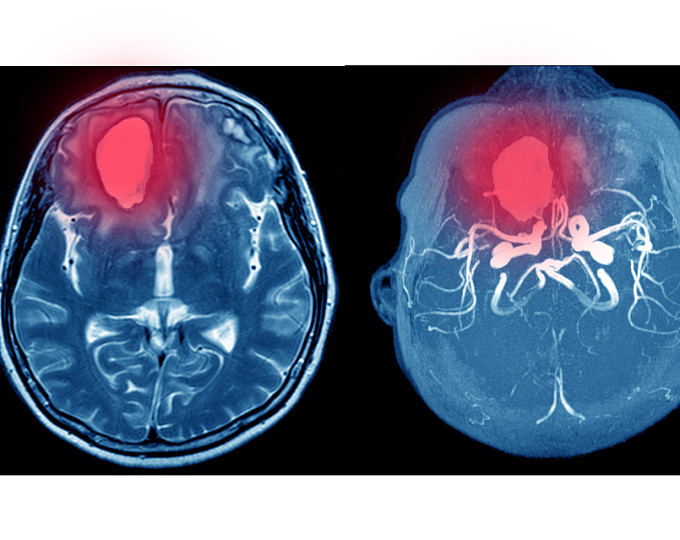

Риск рецидива  внутримозгового кровотечения после возобновления антикоагулянтной терапии у пациентов с механическим клапаном

У пациентов с механическим клапаном возобновление антикоагулянтной терапии после внутимозгового кровотечения вызывает много вопросов с позиции баланса польза-риски.

Целью систематического обзора и мета-анализа оценить риск ишемического инсульта и риск рецидива внутримозгового кровотечения после возобновления терапии варфарином у пациентов с эпизодом внутримозгового кровотечения.

У пациентов с механически клапаном с внутримозговым кровотечением возобновление антикоагулянтной терапии было связано с частотой рецидивов внутримозгового кровотечения 11,4% и частотой ишемического инсульта 6,1 % во время приостановления терапии.